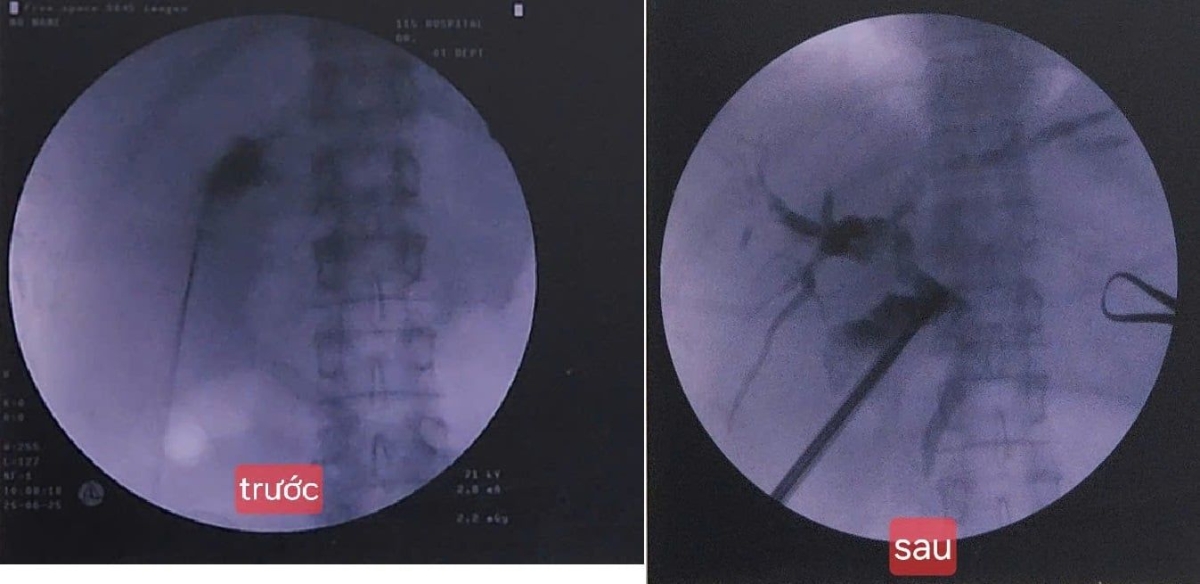

Cũng là một ca bệnh đặc biệt, đầu tháng 8 vừa qua, TS.BS. Nguyễn Quang Huy, Trưởng Khoa Ngoại tổng hợp, Bệnh viện Nhân dân 115 (TP.HCM), cho biết bệnh viện đã thực hiện thành công kỹ thuật tán sỏi túi mật xuyên gan qua da. Kỹ thuật mới này lần đầu tiên được triển khai tại TP HCM.

Theo BS Huy, bệnh nhân nhập viện trong tình trạng sỏi vùng cổ túi mật gây chèn ép ống gan chung và ống mật chủ, dẫn đến tắc mật. Đây là biến chứng nghiêm trọng có thể gây viêm tụy, nhiễm trùng đường mật hoặc thậm chí suy gan nếu không được xử lý kịp thời. Với những trường hợp như vậy, điều trị thông thường là phẫu thuật cắt túi mật. Tuy nhiên, bệnh nhân có nhiều bệnh nền, thể trạng yếu nên việc phẫu thuật gây mê tiềm ẩn nguy cơ cao.

Trước tình hình đó, ê-kíp đã quyết định sử dụng thiết bị chuyên dụng đi xuyên gan qua da để tiếp cận túi mật, sau đó tán sỏi bằng sóng xung kích hoặc công nghệ hiện đại khác dưới hướng dẫn hình ảnh (siêu âm, chụp C-Arm, DSA...). Ưu điểm nổi bật của kỹ thuật này là không cần gây mê toàn thân; ít đau, hồi phục nhanh; giảm nguy cơ biến chứng cho bệnh nhân yếu; giữ lại được túi mật, cơ quan có vai trò quan trọng trong tiêu hóa.